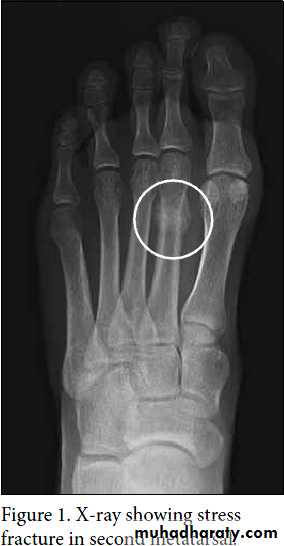

Metatarsal stress fracture ( March fracture)

Young adult (a military recruit or a nurse) or osteoporotic women affected usually, the foot may become painful and slightly swollen after overuse. A tender lump is palpable just distal to the midshaft of a metatarsal bone (usually the second metatarsal) .X-ray appearance may at first be normal but a radioisotope scan will show an area of intense activity in the bone. Later a hairline crack may be visible and later on a callus. No displacement occurs and neither reduction nor splintage is necessary. The forefoot may be supported with an elastic bandage and normal walking is encouraged.